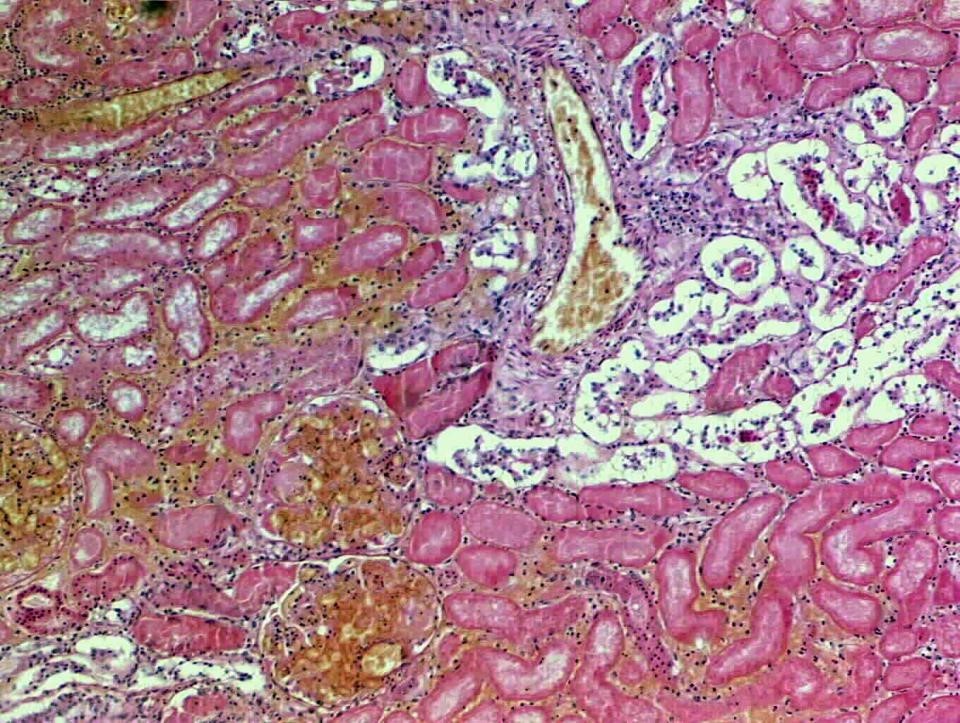

Renal cortical necrosis - kidney is diffusely damaged due to microthromi.

Hypereosinophilic cells

Tubular structures are filled with degenerate necrotic debris

Inflammatory cells have infiltrated interstitium

Gram-ve microthrombi

Fibrin and cell debris within tubular lumen. Hypereosinophilic cells w/out nuclei.

Causes: